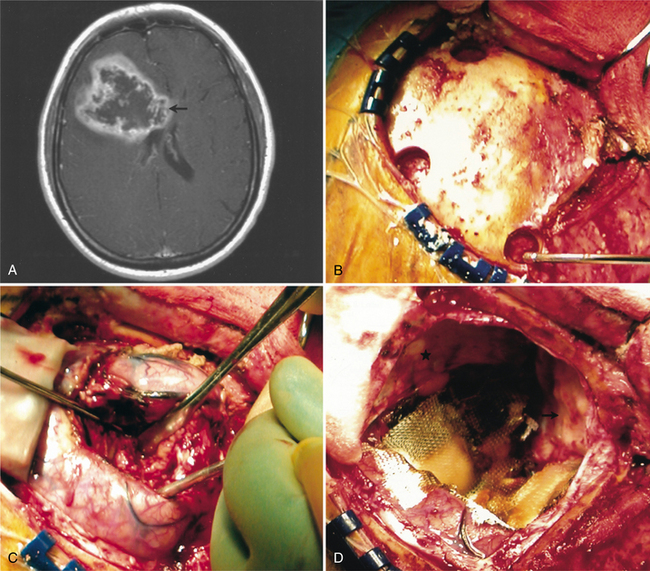

Pathogenesis.: Anaplastic astrocytomas, grades III and IV, are diffusely infiltrative tumors that invade into the cerebral parenchyma. They typically involve the white matter of the cerebral hemispheres but may occur primarily in grey matter as well as in other areas of the CNS.130 They often contains a mix of cells and cell grades but are graded by the highest-grade cell seen in the tumor. GBM is a particularly rapidly growing, aggressive, infiltrative tumor that tends to invade both cerebral hemispheres via the corpus callosum. See Fig. 30-6 for a GBM MRI and intraoperative pictures. A GBM is a pinkish grey or multicolored, well-demarcated mass with scattered areas of grossly visible hemorrhage. The blood vessels show endothelial proliferation: it is a highly vascular tumor, with vascular endothelial growth factor (VEGF) implicated, suggesting that the malignant progression from low-grade astrocytoma to GBM includes an “angiogenic switch.”130 There may be areas of cystic degeneration and a central area of creamy necrosis. The histologic distinction of an anaplastic astrocytoma from a glioblastoma is based largely on the absence or presence of tumor necrosis139 and microvascular proliferation.130 Microscopically, the tumor is pleomorphic (having various distinct forms) and hypercellular, with the cells showing hyperchromatic nuclei. There are many mitoses, giant cells, and young glial forms.

Figure 30-6 Magnetic resonance imaging (MRI) and intraoperative pictures of a patient with a right frontal glioblastoma multiforme. A, An axial T1-weighted MRI scan. The enhancing lesion demonstrates central necrosis and is causing mass effect. Infiltration along the corpus callosum is also shown (arrow). B, A frontal craniotomy is being performed. Burr holes have been placed and will be connected for bony removal. C, The brain has been incised and the tumor is being removed using a combination of suction and blunt dissection. D, The tumor and frontal lobe have been resected. The cut edge of the brain is seen at the lower left. The resection cavity has been lined with carmustine polymer (Gliadel) wafers and covered with a layer of Surgicel for hemostasis. (From Townsend CM Jr: Sabiston textbook of surgery, ed 17, Philadelphia, 2004, Saunders.)